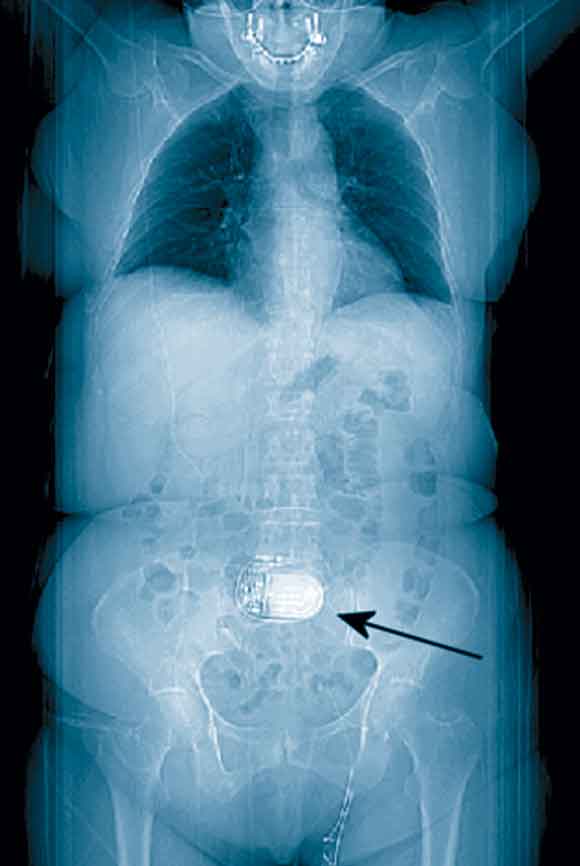

Review of the patient’s previous medical records revealed, on a thoracoabdominal image derived from computed tomography data, a foreign body in the central abdominal region (Box 2). Questioning of the patient after the angioplasty revealed that this was an electrostimulator (Itrel II, Medtronic, Minneapolis, USA) implanted a few years earlier as part of a dynamic graciloplasty to treat faecal incontinence. An ECG performed 12 hours after the angioplasty with the device deactivated (by the patient’s control programmer) produced an ECG tracing free of artefacts (Box 1B).

Intrathoracic devices are usually discovered on physical examination or standard chest x-ray, but devices in other parts of the body may not be obvious. In dynamic graciloplasty to treat anal incontinence, the gracilis muscle is transposed around the anal canal and electronically stimulated by a device placed in a subcutaneous pocket in the abdominal wall.4 In our case, this device led to ECG artefacts potentially interfering with the ability to diagnose the acute myocardial infarction.